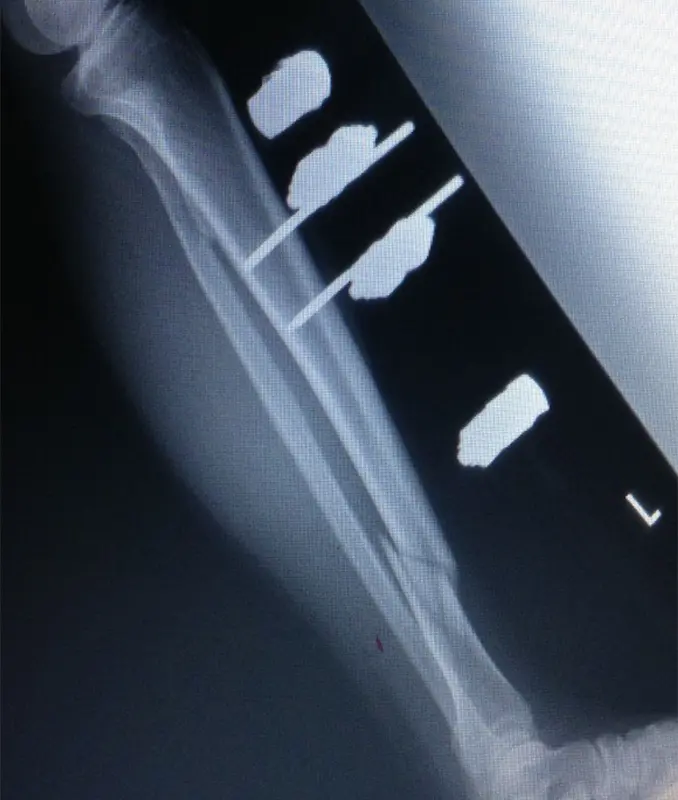

(図3)CT